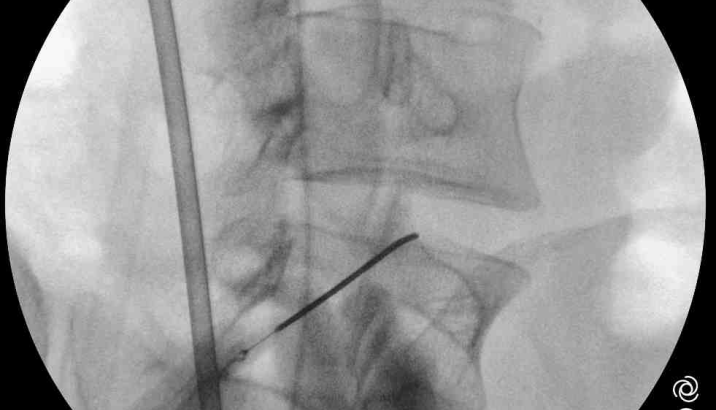

O que é a neuroestimulação? A neuroestimulação é uma técnica médica que utiliza impulsos elétricos de baixa intensidade para modular a atividade do sistema nervoso central e periférico. Ao interferir com os sinais de dor que vão da periferia do nosso corpo para o cérebro, este tratamento oferece um alívio significativo e duradouro para muitas […]